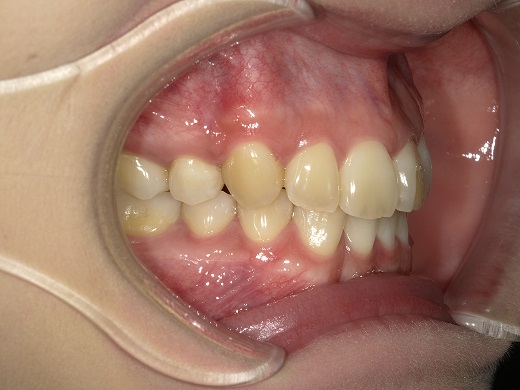

治療前左側

治療中左側

治療後左側